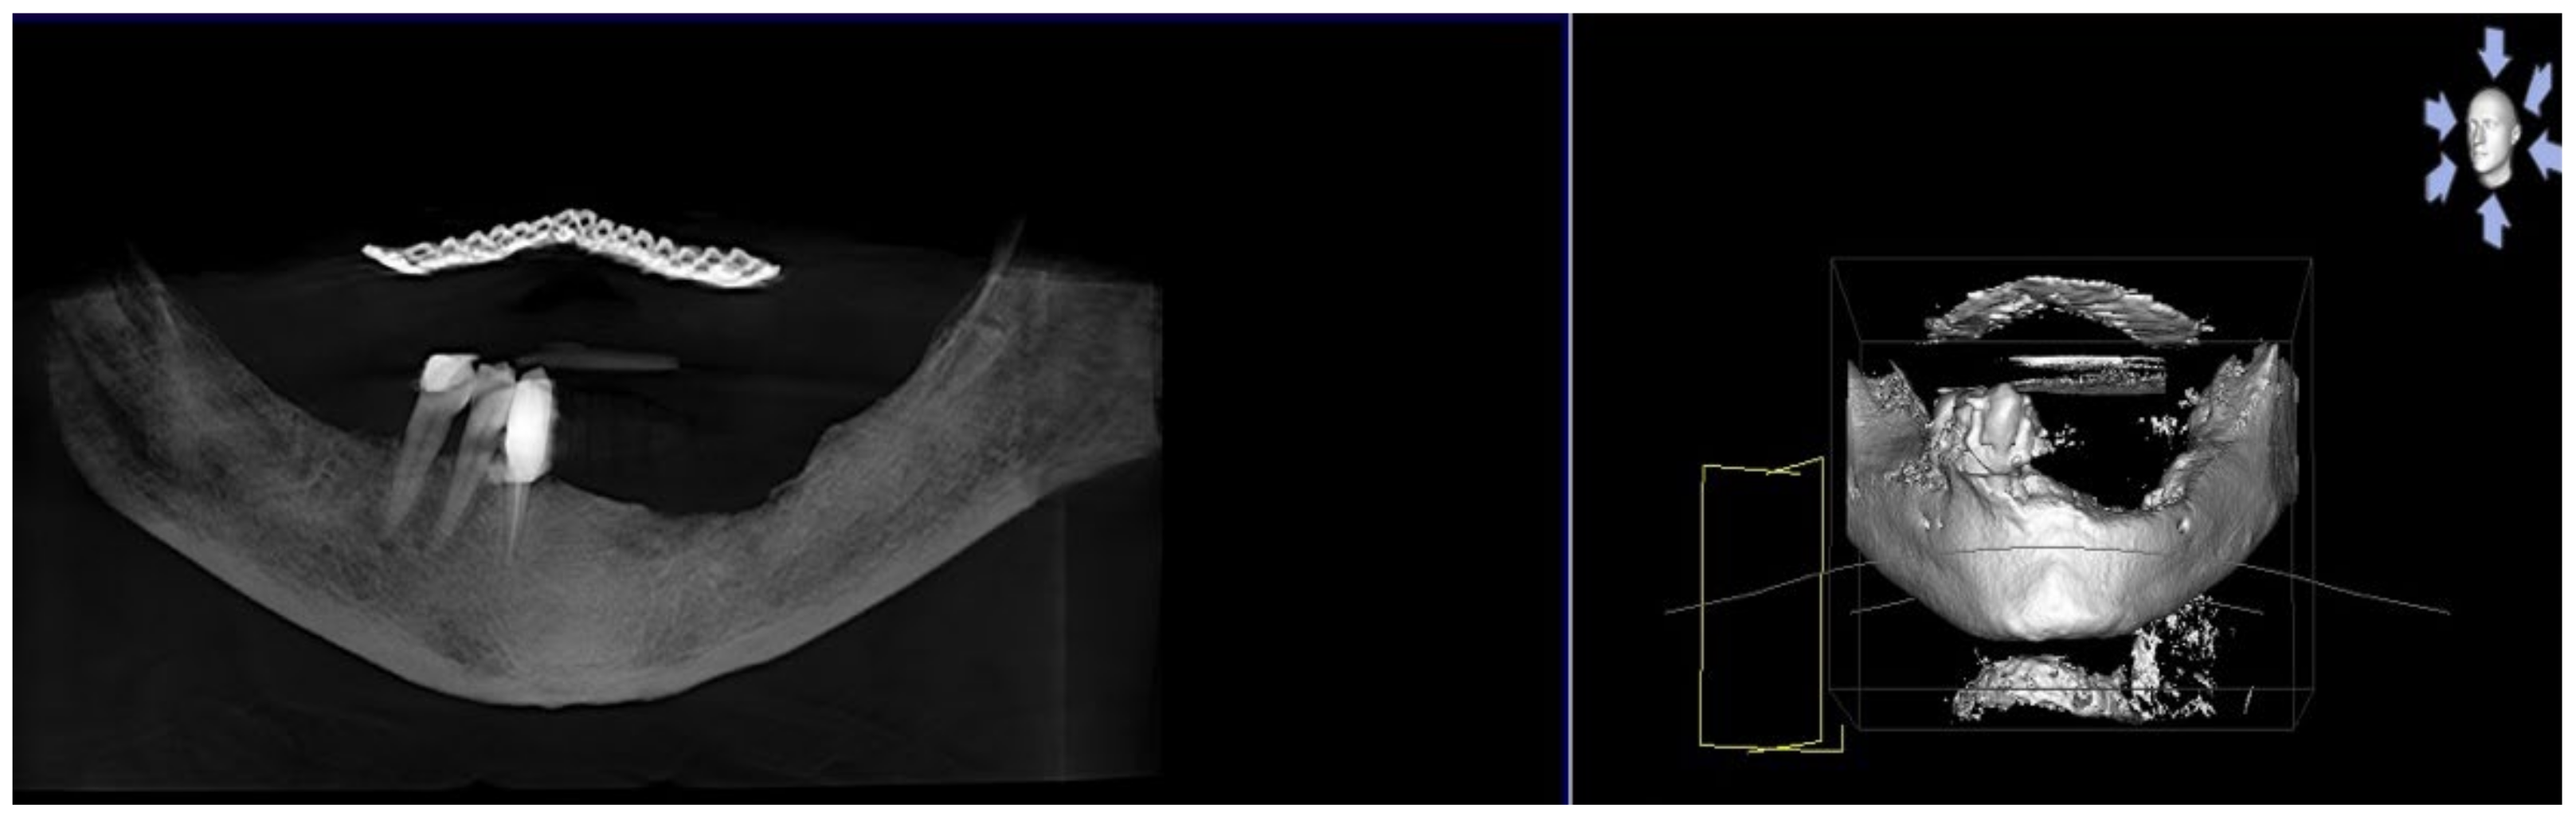

3.1. Clinical Case 1

3.2. Clinical Case 2

3.3. Clinical Case 3

3.4. Clinical Case 4

3.5. Clinical Case 5

3.6. Clinical Case 6